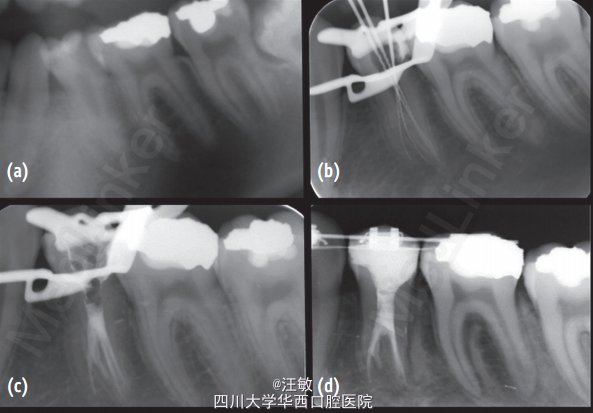

患者因下颌第二前磨牙疼痛就诊

检查发现左下颌第二前磨牙远中龋坏,探(-),叩(-),无牙髓活力。X线片示根尖周组织无明显异常。

诊断为35牙慢性牙髓炎,拟进行35牙根管。治疗过程中发现35牙为多根管,故使用CBCT和三维重建辅助进行根管治疗